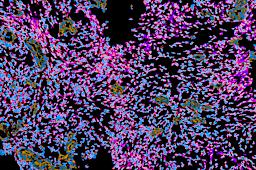

Pancreatic ductal adenocarcinoma is a lethal disease with limited treatment options and poor survival. We studied 83 spatial samples from 31 patients (11 treatment-naïve and 20 treated) using single-cell/nucleus RNA sequencing, bulk-proteogenomics, spatial transcriptomics and cellular imaging. Subpopulations of tumor cells exhibited signatures of proliferation, KRAS signaling, cell stress and epithelial-to-mesenchymal transition. Mapping mutations and copy number events distinguished tumor populations from normal and transitional cells, including acinar-to-ductal metaplasia and pancreatic intraepithelial neoplasia. Pathology-assisted deconvolution of spatial transcriptomic data identified tumor and transitional subpopulations with distinct histological features. We showed coordinated expression of TIGIT in exhausted and regulatory T cells and Nectin in tumor cells. Chemo-resistant samples contain a threefold enrichment of inflammatory cancer-associated fibroblasts that upregulate metallothioneins. Our study reveals a deeper understanding of the intricate substructure of pancreatic ductal adenocarcinoma tumors that could help improve therapy for patients with this disease.